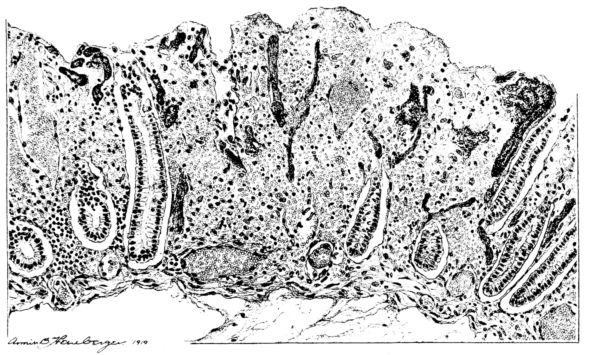

FIG. I. AUTOPSY NO. 99. ACUTE HEMORRHAGIC AND ULCERATIVE LARYNGOTRACHEITIS.

FIG. I. AUTOPSY NO. 99. ACUTE HEMORRHAGIC AND ULCERATIVE LARYNGOTRACHEITIS.

Early in the disease the congestion and the hemorrhages that have been described in the mucous membrane of the nasopharynx (14 and 94) are also conspicuous features in the lining of the trachea and bronchi (Fig. I). This membrane is swollen, turgid, red, and covered by a copious, mucous exudate which may be clear, but much more frequently is blood-stained or opaque and yellowish in color. The blood, variable in amount, may be fresh and red; and after the mucous exudate on the surface is removed, more intense red foci stand out on the congested base (47, 90, 157). Frequently, as the bronchi are approached, the red color of the mucosa becomes more intense and may have a garnet tinge. Membranes such as are encountered in the more usual necrotizing inflammatory processes, like diphtheria, have not occurred in the trachea and larger bronchi in this series (108, 128, 157).[3] The exudate peels off readily, and as indicated above, leaves a velvety red surface, 14dotted here and there with darker or more intensely red foci. Small ulcerations of the mucosa occur, but are inconspicuous (82, 156). As the finer ramifications of the bronchi are approached, the accumulation of the exudate in their lumina becomes more and more marked, and on cross section of the lung, they often stand out conspicuously on account of their increased size and projecting, seromucous, blood-stained content (101, 149, 162).